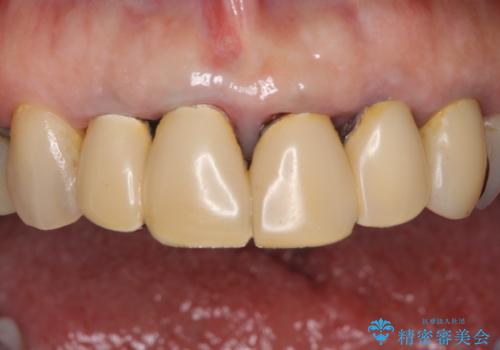

汚れてしまった保険のクラウン 前歯のオールセラミック

- 保険診療で装着した前歯のクラウンの変色を気にして来院された患者様です。

保険診療では樹脂を用いた素材で製作するため、水分が吸収されやすく、一緒に色素が取り込まれるために変色をしてしまいます。

また、裏打ちに主に銀を用いた金属材料を使用するため、金属自体が黒くなったり、イオンとなり溶け出したりして、歯肉ラインが黒くなってしまうことがあります。

金属の土台を歯の色に近いものへと変更した上で、オールセラミッククラウンにて補綴することとしました。